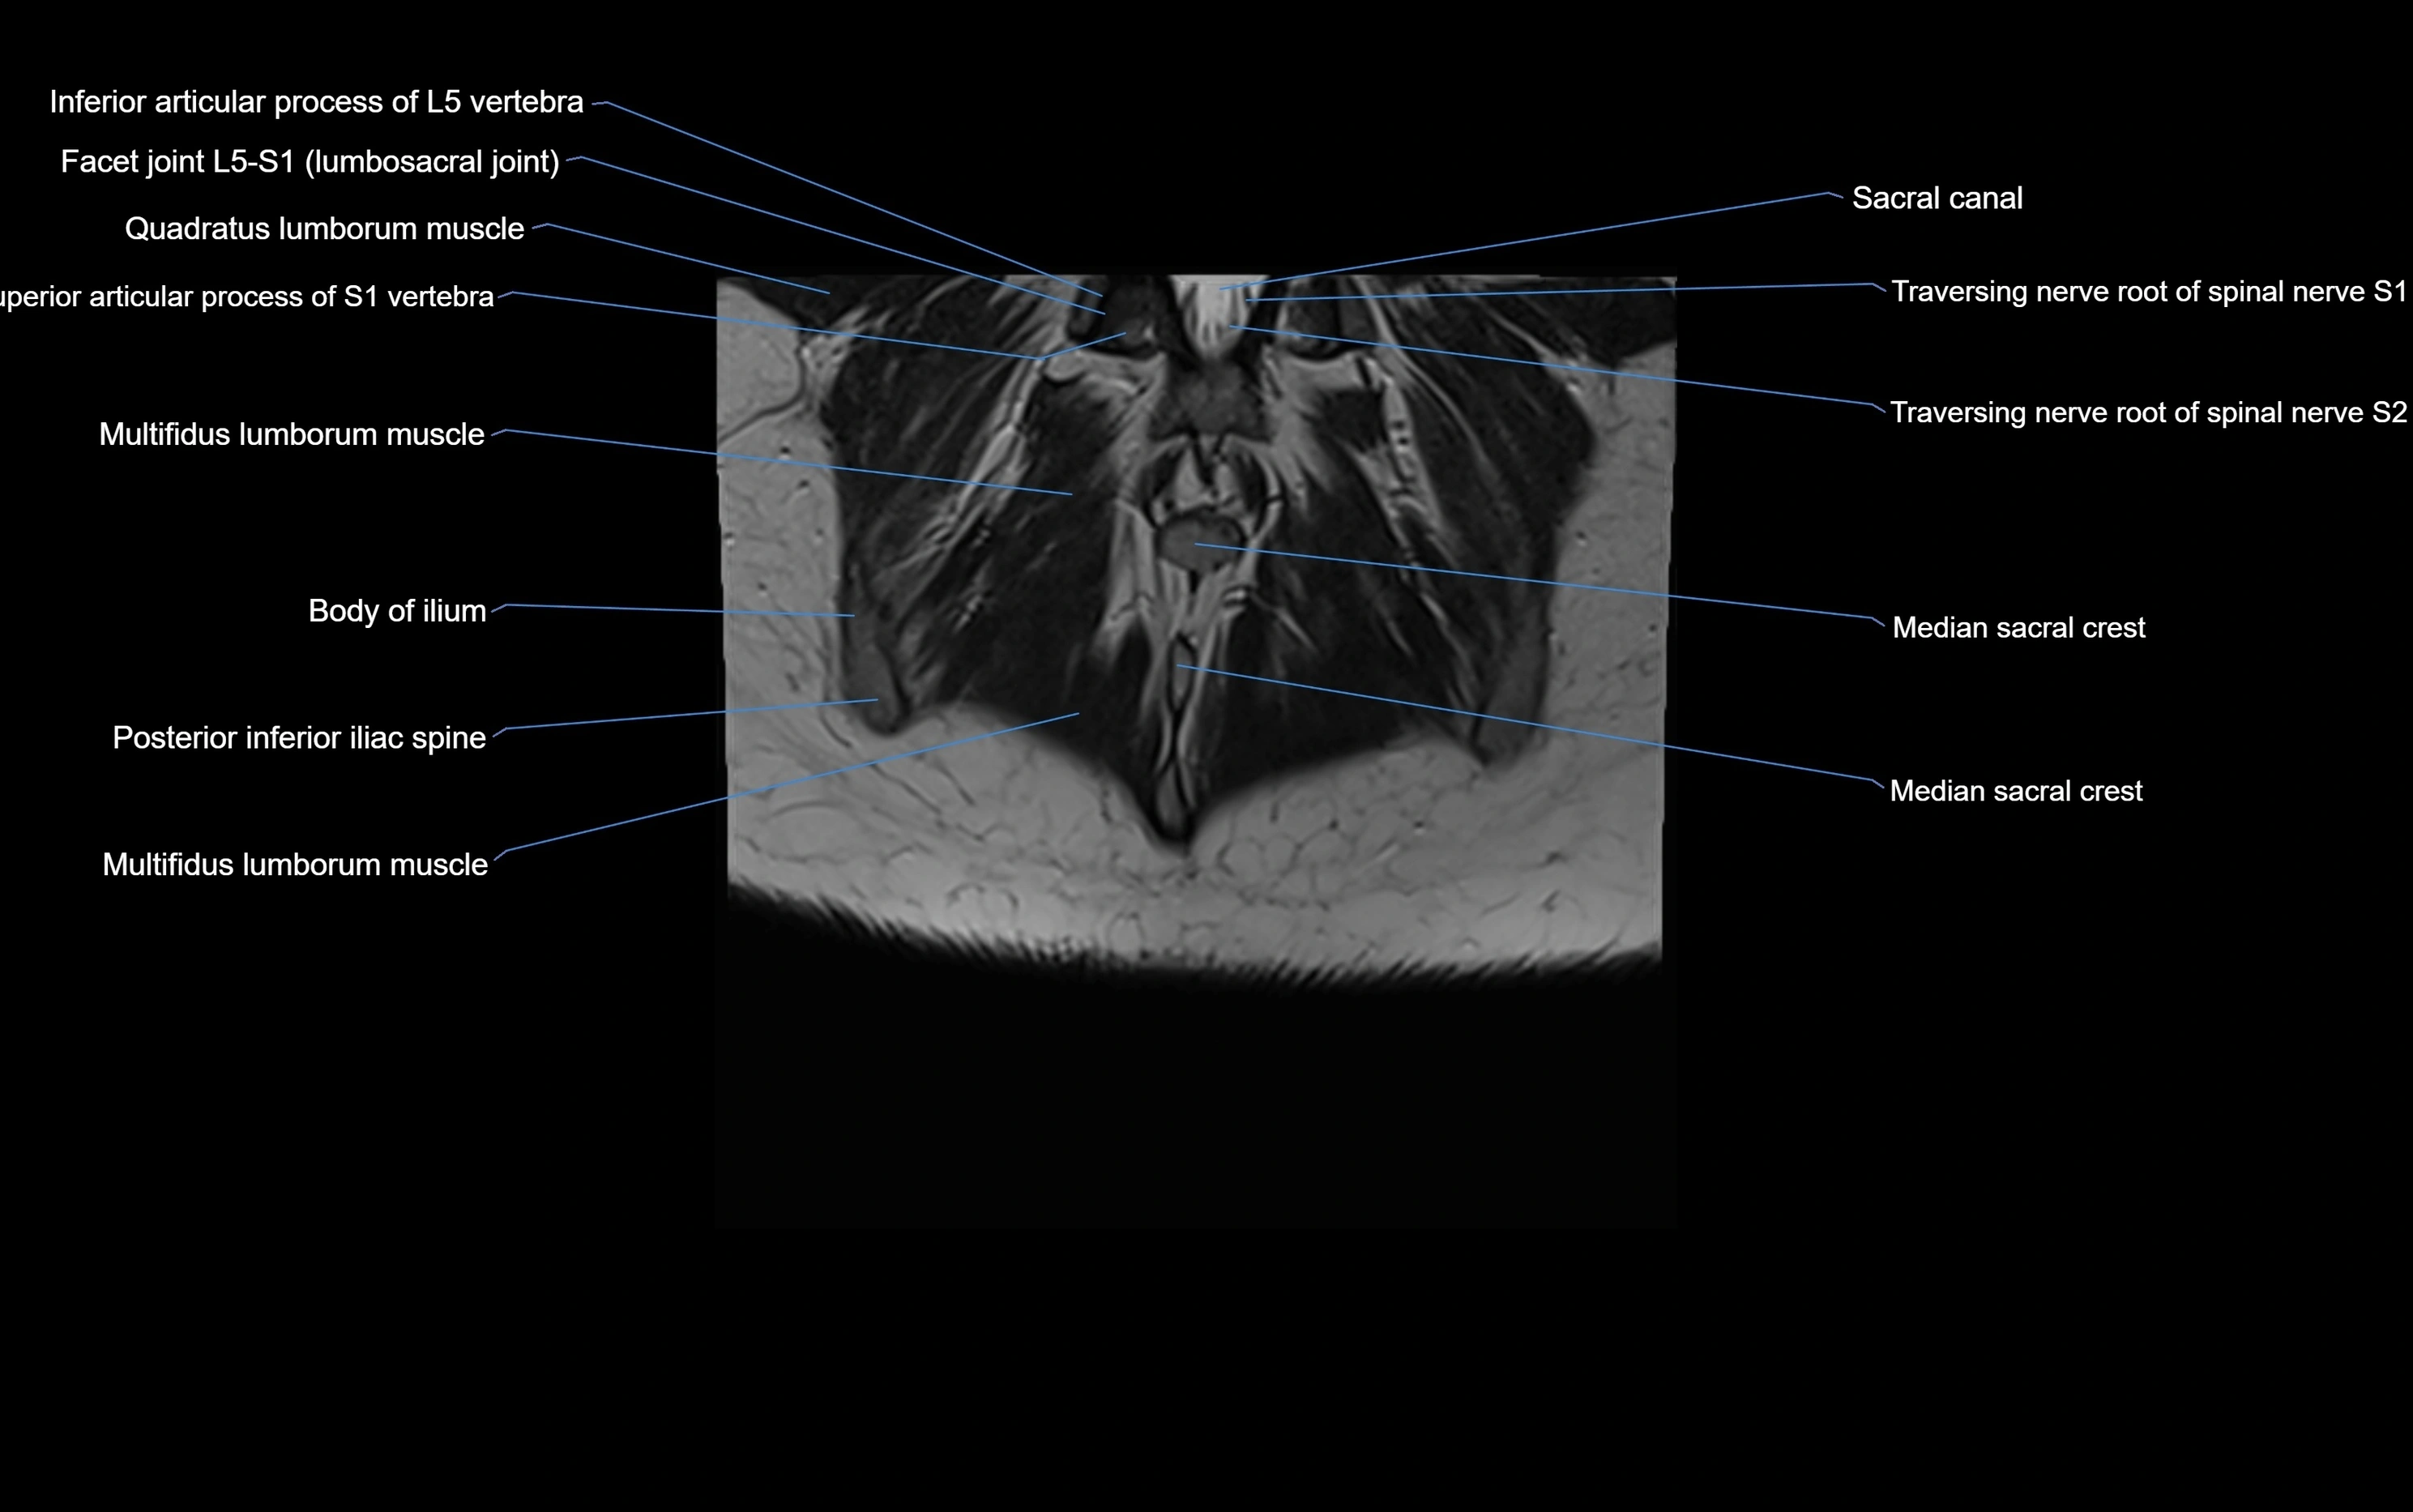

MRI Appearance

T1-weighted images:

• Cortical bone appears very low signal (dark); marrow shows intermediate signal

• Iliac fossa fat is bright against low-signal cortex

T2-weighted images:

• Cortical bone remains dark

• Marrow signal varies depending on fat content; edema or tumor shows hyperintensity

MRI image

image